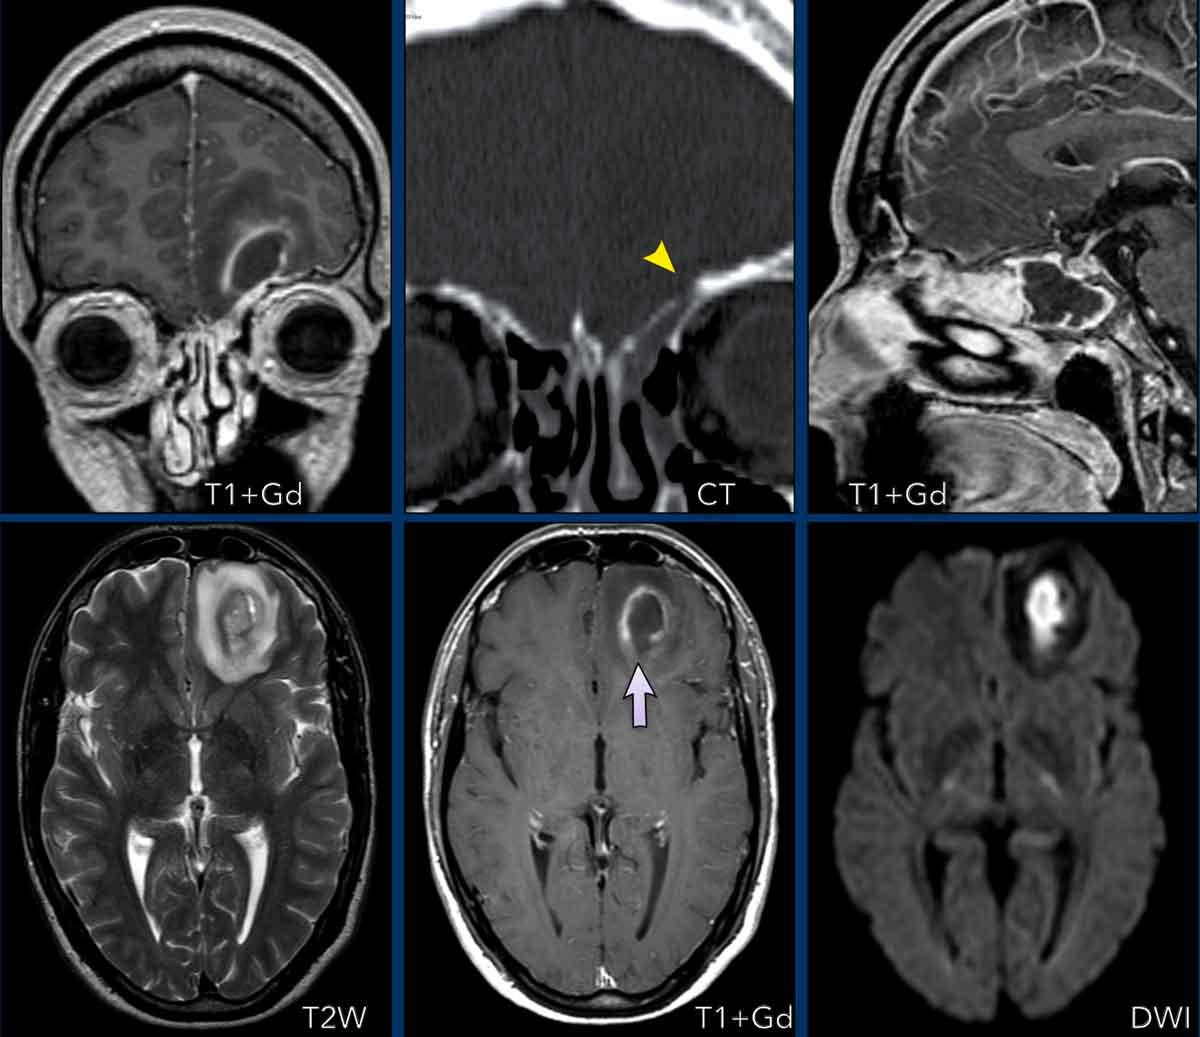

Nang có Nốt

Trong kiểu ngấm thuốc này, tuổi của bệnh nhân đóng vai trò quan trọng trong chẩn đoán phân biệt.

Ở trẻ em, chẩn đoán phân biệt bao gồm U nguyên bào thần kinh đệm lông (Pilocytic astrocytoma), U hạch thần kinh đệm (Ganglioglioma) và U nguyên bào thần kinh đệm đa hình xantho (Pleomorphic xanthoastrocytoma – PXA).

Ở người lớn, u nguyên bào mạch máu (hemangioblastoma) có khả năng cao hơn.

U nguyên bào thần kinh đệm lông (Pilocytic astrocytoma)

U nguyên bào thần kinh đệm lông là khối u não thường gặp nhất ở trẻ em và thường được tìm thấy ở hố sau.

Phẫu thuật cắt bỏ hoàn toàn thường mang lại khả năng chữa khỏi cho bệnh nhân.

Các hình ảnh này của một trẻ 9 tuổi nhập viện vì đau đầu.

Hình ảnh

Có một khối nang lớn ở hố sau gây chèn ép và tắc nghẽn não thất bốn và thân não.

Ghi nhận một nốt đặc ngấm thuốc tương phản, cùng với sự ngấm thuốc của thành nang.

Kết luận

Chẩn đoán có khả năng nhất ở độ tuổi này là u nguyên bào thần kinh đệm lông.

U nguyên bào mạch máu (Hemangioblastoma)

U nguyên bào mạch máu thường gặp nhất ở tiểu não, nơi đây nó là u tân sinh nguyên phát thường gặp nhất ở người lớn.

Ít gặp hơn ở tủy sống.

Khối u bắt đầu là một nốt đặc và dần dần hình thành nang.

Nốt nằm ở phía màng mềm (phần trong của màng não).

Thành nang không phải là một phần của khối u và thông thường không ngấm thuốc, trừ trường hợp có chảy máu trong nang.

Do thành nang không phải là mô u, nên không cần thiết phải cắt bỏ toàn bộ nang.

Các hình ảnh này của một phụ nữ 63 tuổi mắc bệnh von Hippel-Lindau.

Hãy quan sát kỹ. Dấu hiệu nào khó nhận thấy?

Có một nang lớn với một nốt nhỏ ngấm thuốc ở bán cầu tiểu não phải.

Thành nang không ngấm thuốc.

Lưu ý nốt u nằm ở phía màng mềm (mũi tên).

Có thêm hai nốt nhỏ ngấm thuốc ở mặt sau của tiểu não.

Đa u hầu như luôn liên quan đến bệnh von Hippel-Lindau.

Các hình ảnh này của một nam giới 29 tuổi.

Tổn thương dạng nang với thành không ngấm thuốc và một nốt ngấm thuốc nằm ở phía màng mềm.

Hình ảnh điển hình của u nguyên bào mạch máu.

Khi phẫu thuật cắt bỏ khối u này, phẫu thuật viên chỉ cần lấy bỏ phần nốt.